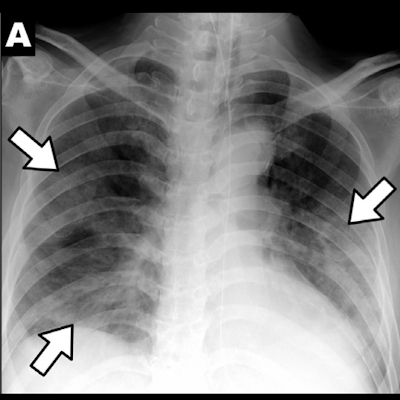

They found that three of the nine patients (33%) had parenchymal abnormalities on chest x-ray, and most of these were peripheral consolidations. However, chest CT images showed double lung involvement in eight of the nine patients. In fact, a total of 77 pulmonary lesions were identified on chest CT in the patient cohort; of these, 39% were patchy lesions, 13% were large confluent lesions, and 48% were small nodular lesions. In 78% of these CT-identified lesions, peripheral lung fields were involved, while in 67%, posterior lung fields were involved.

Since most of the pulmonary lesions identified on chest CT weren't clear on chest x-ray, it's important that radiologists be up to date on what to look for on CT, according to the team.

"Clinicians and radiologists should become familiar with the CT findings of COVID-19 and the limitations of chest radiographs in evaluating pneumonia to manage the COVID-19 outbreak," the group concluded.